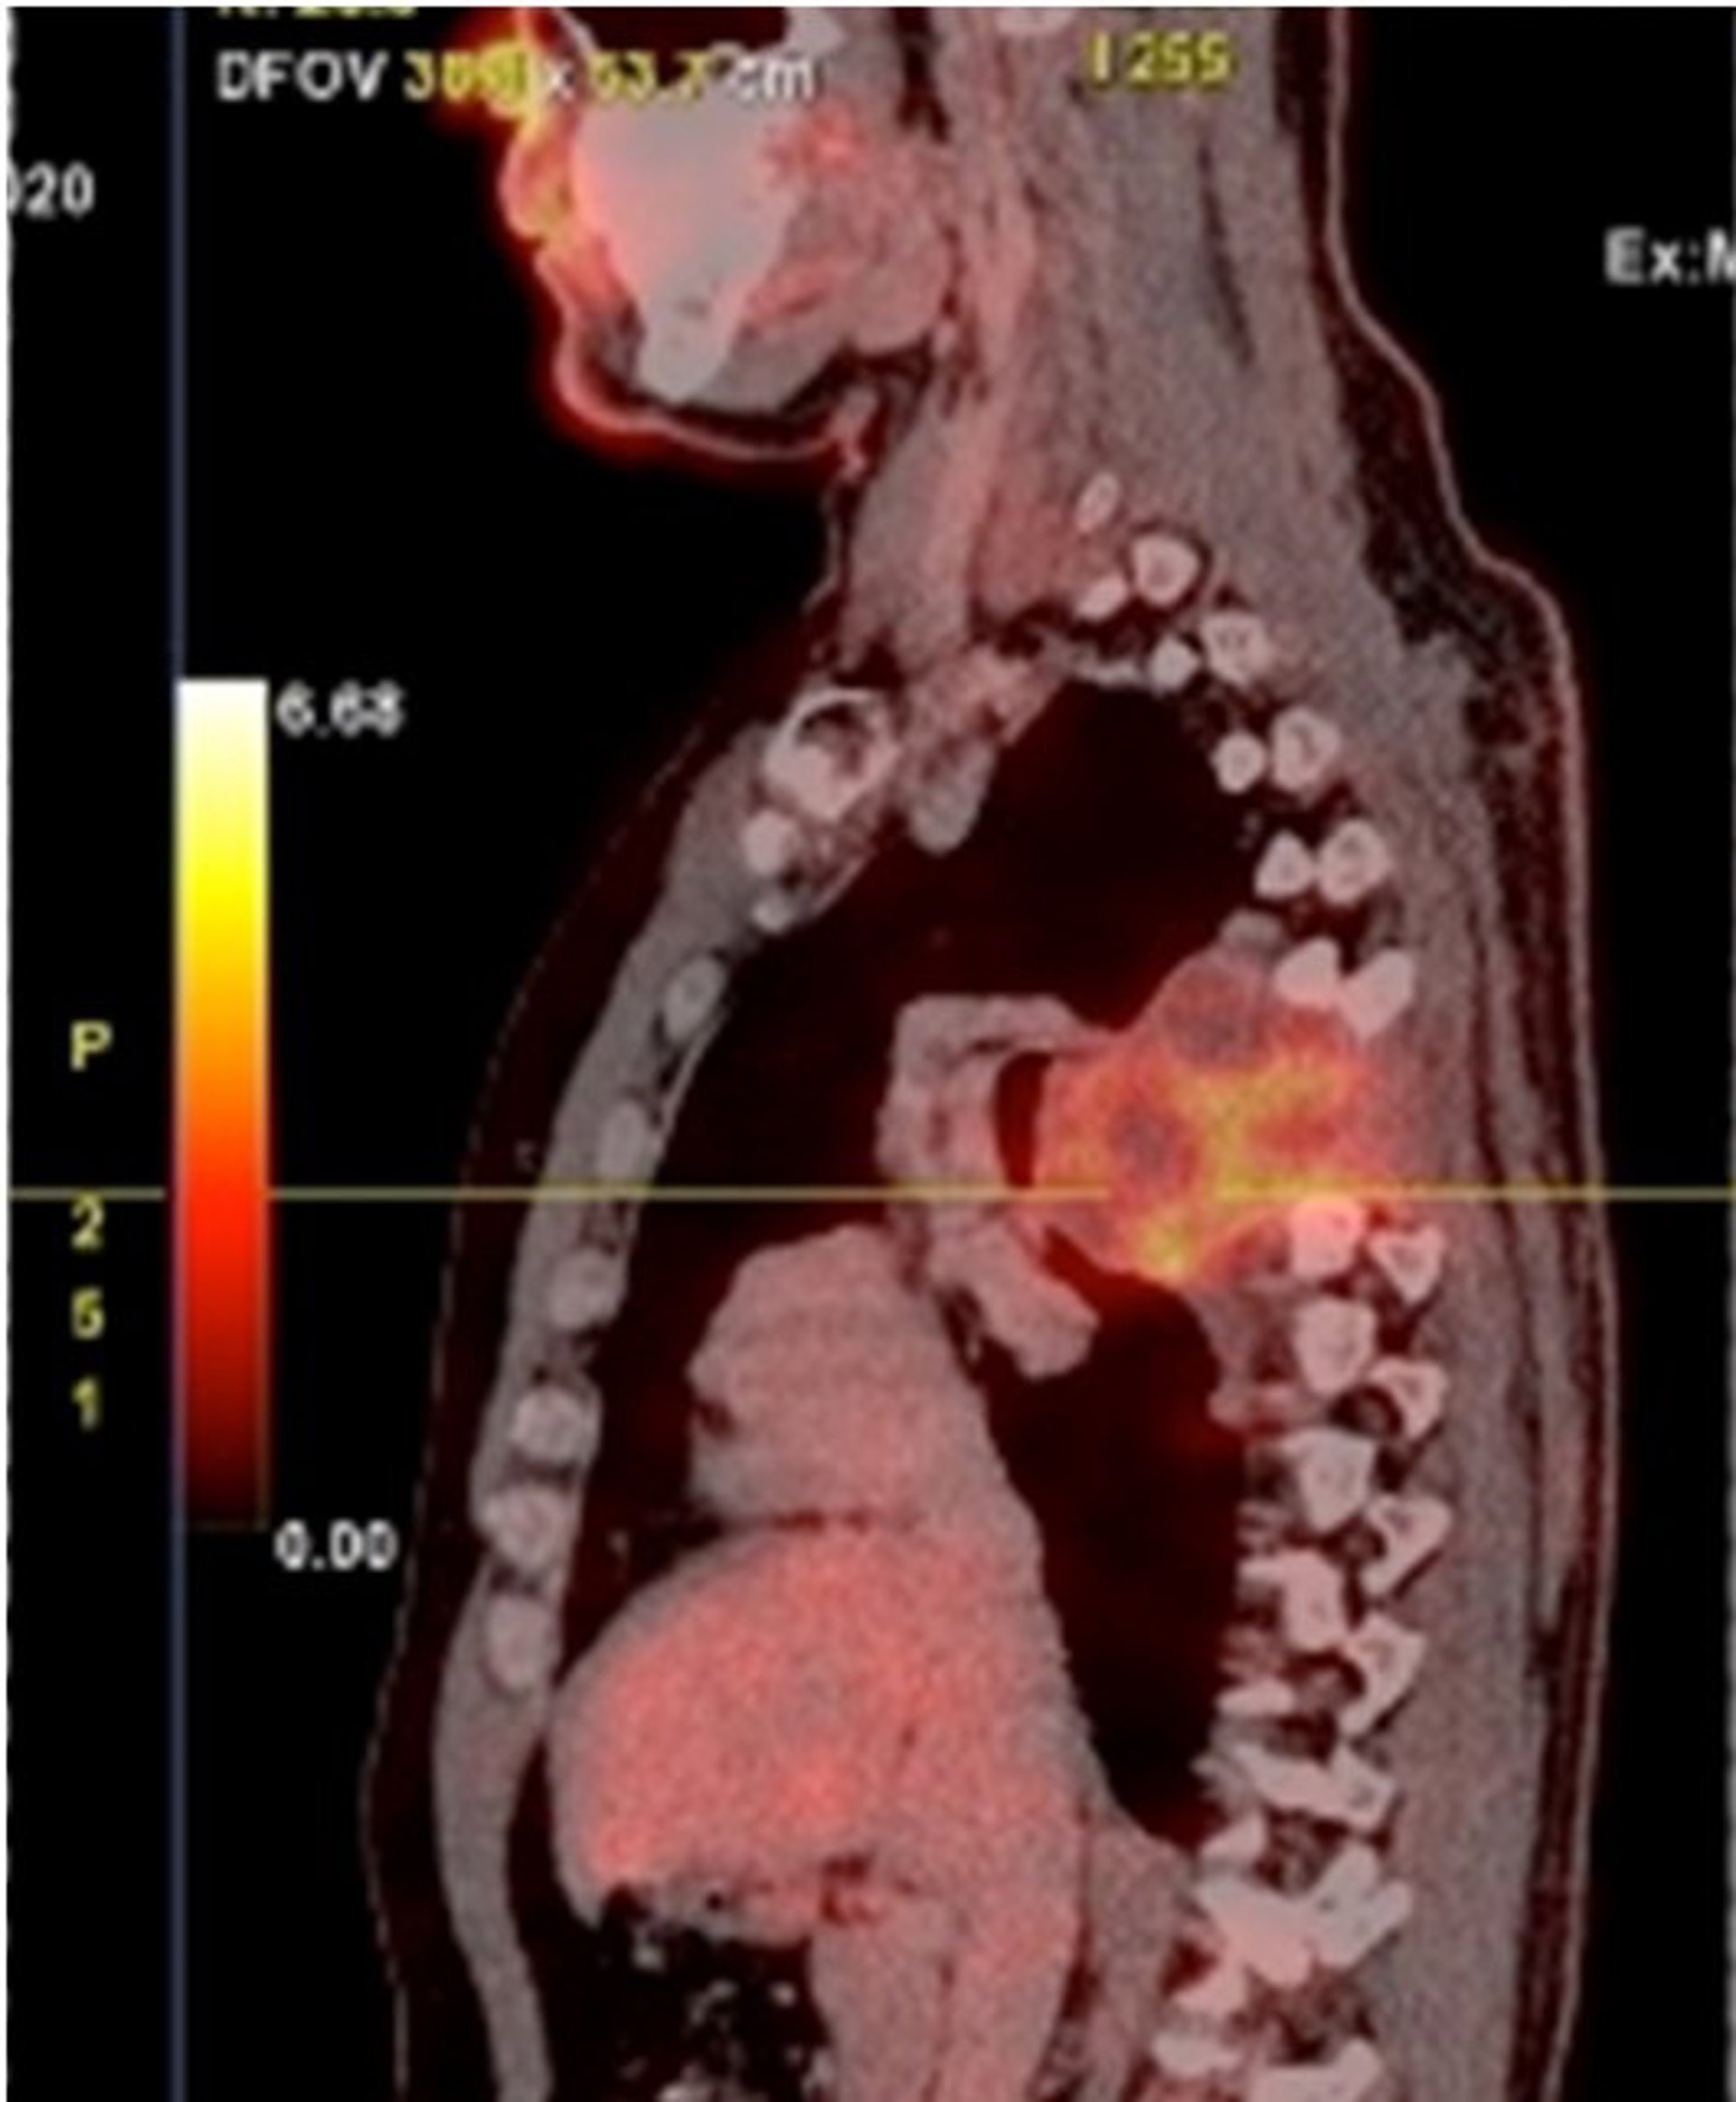

PET del paciente portugués

PET del paciente portugués - VITHAS

El equipo del doctor Antonio Martín Benlloch ha operado en el Hospital Vithas Valencia 9 de Octubre un condosarcoma de gran tamaño que comprometía tres vértebras y a la caja torácica, tras una intervención que ha precisado de 24 horas de quirófano. El crecimiento del volumen tumoral del paciente, un ciudadano portugués que fue remitido al centro valenciano por su experiencia, desplazaba el mediastino: aorta, esófago y pulmón.

El paciente, José Miguel, de 42 años, comenzó a padecer dolor de espalda. Las molestias se agudizaron y persistieron. Finalmente llegó el diagnóstico: un condrosarcoma afectaba a los cuerpos vertebrales T5, T6 y T7 y a varias costillas. Y en su crecimiento desplazaba, además de a la aorta y esófago, a la carina y a los vasos pulmonares. La resistencia de este tipo de tumores a tratamientos de radio y quimioterapia hacía imprescindible la resección del tumor.